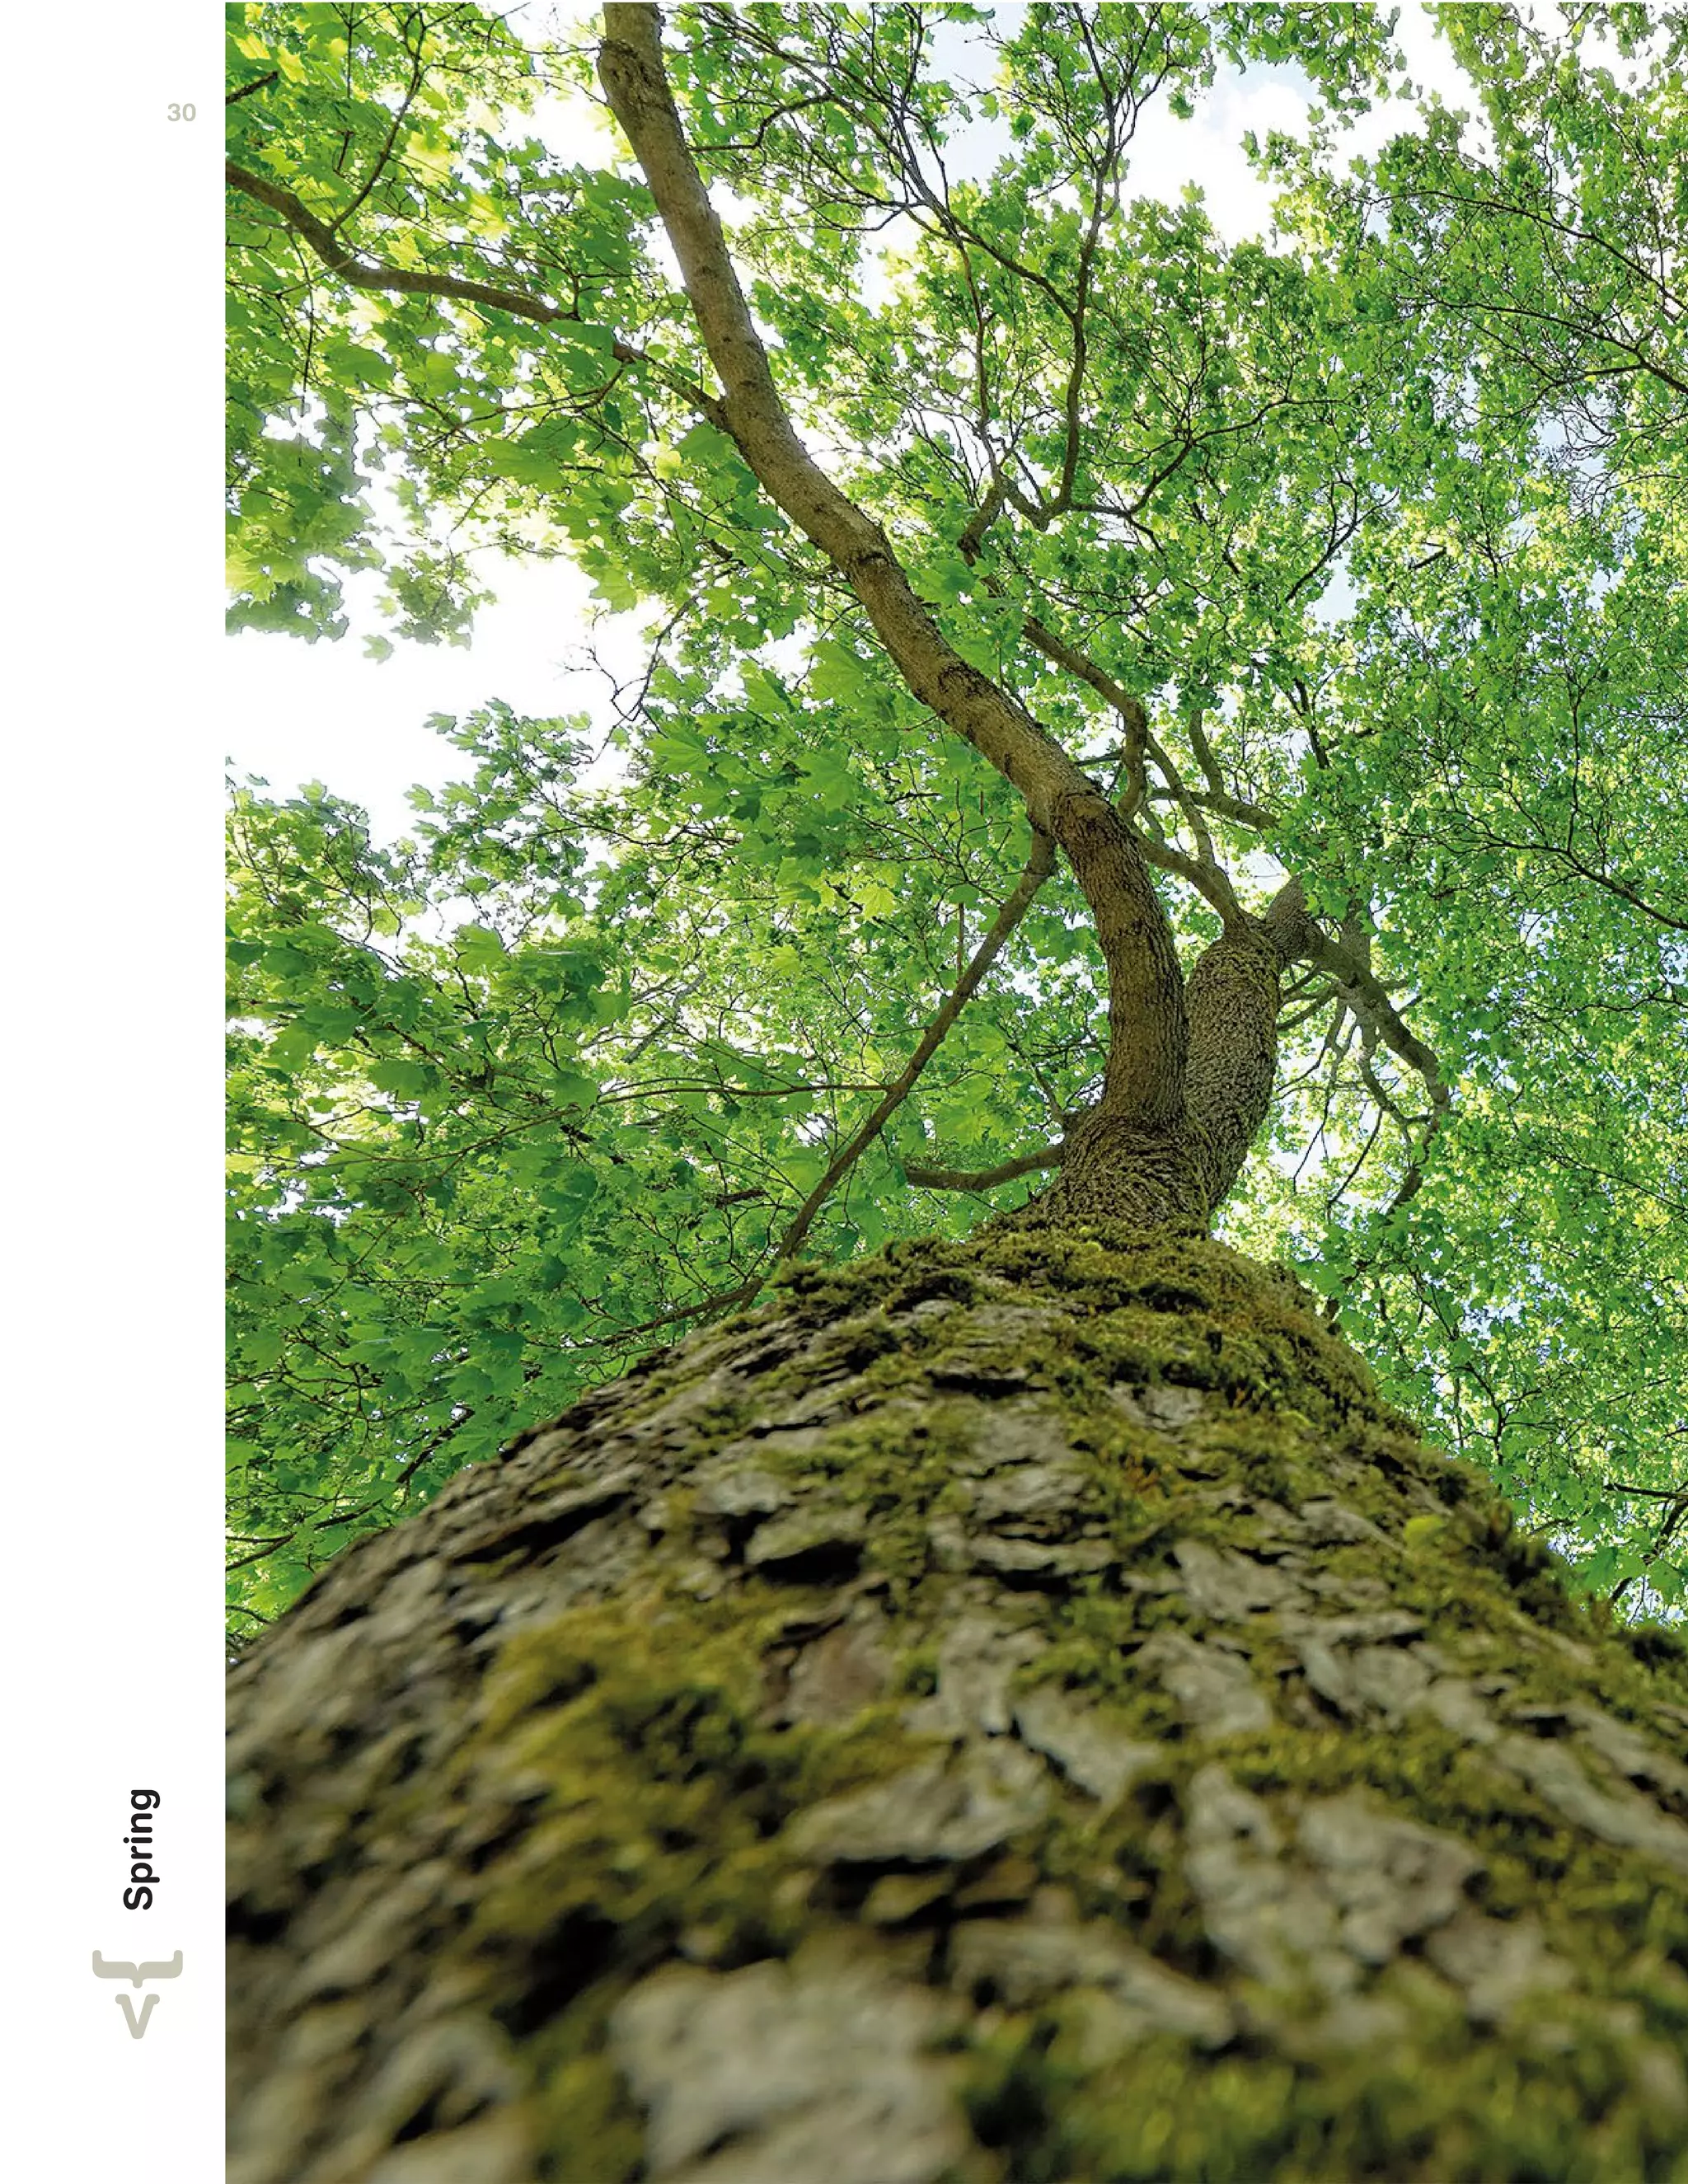

The document highlights Vaadin's role in bridging the gap between HTML5 and Java platforms, showcasing various applications and case studies that underscore the importance of user experience in software development. It includes information on talented professionals at Vaadin, their workplace culture, and details about upcoming conferences centered around GWT and Vaadin technologies. Overall, it serves as an inspirational magazine aimed at developers and companies looking to leverage these powerful frameworks for building business applications.